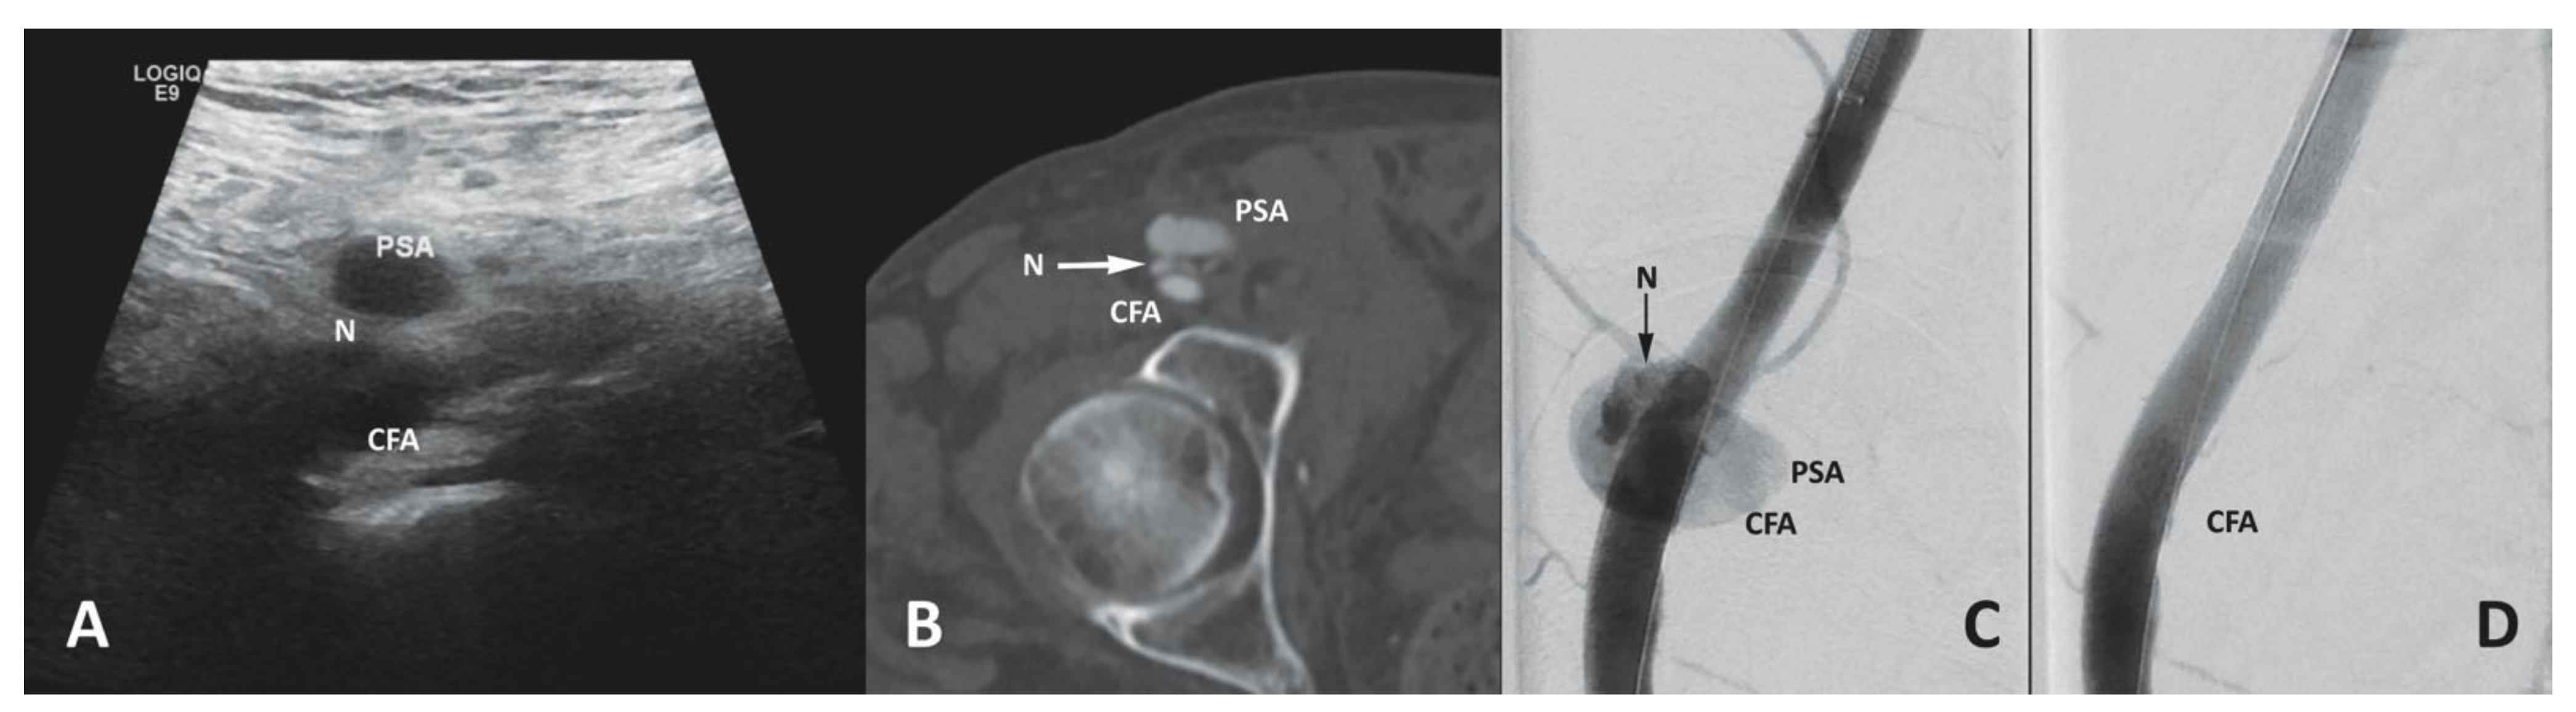

3.6.4. Access Site Pseudoaneurysm